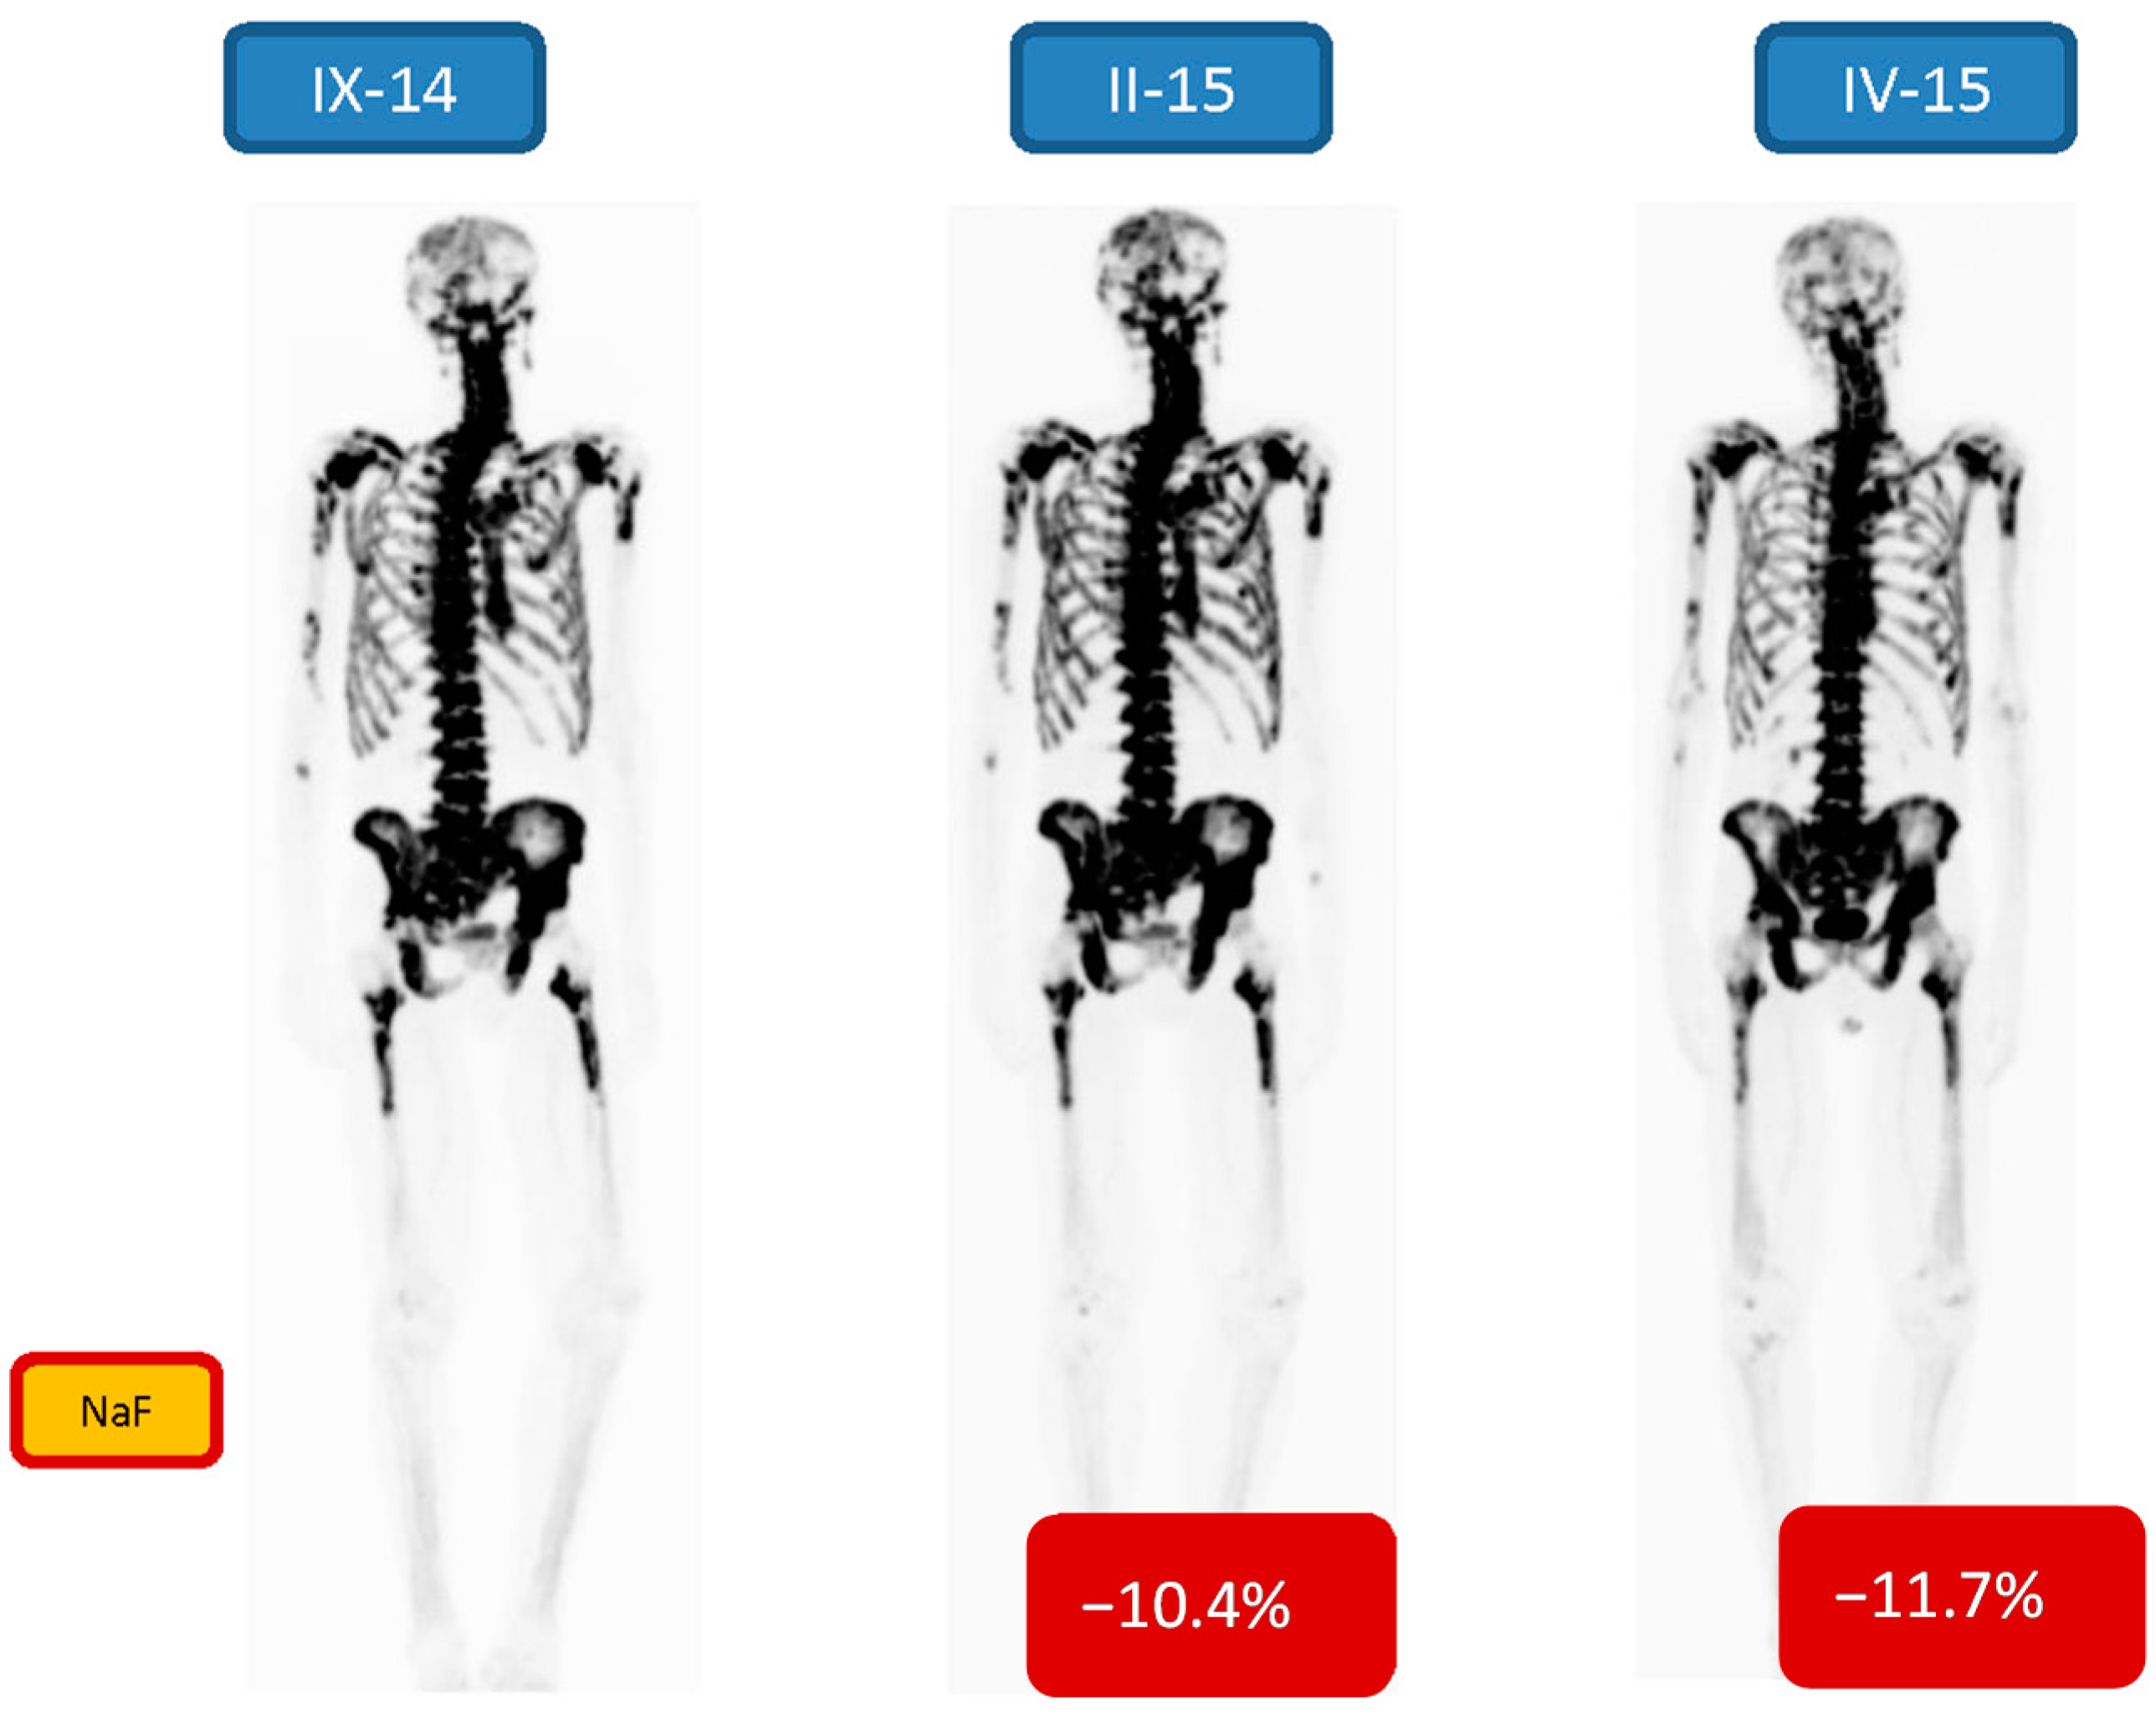

| 6 m/69 | Bone 3/3 | −10.4/−11.7 | 7 24.13 MBq | PR | Goserelin, Denosumab, Enzalutamide |